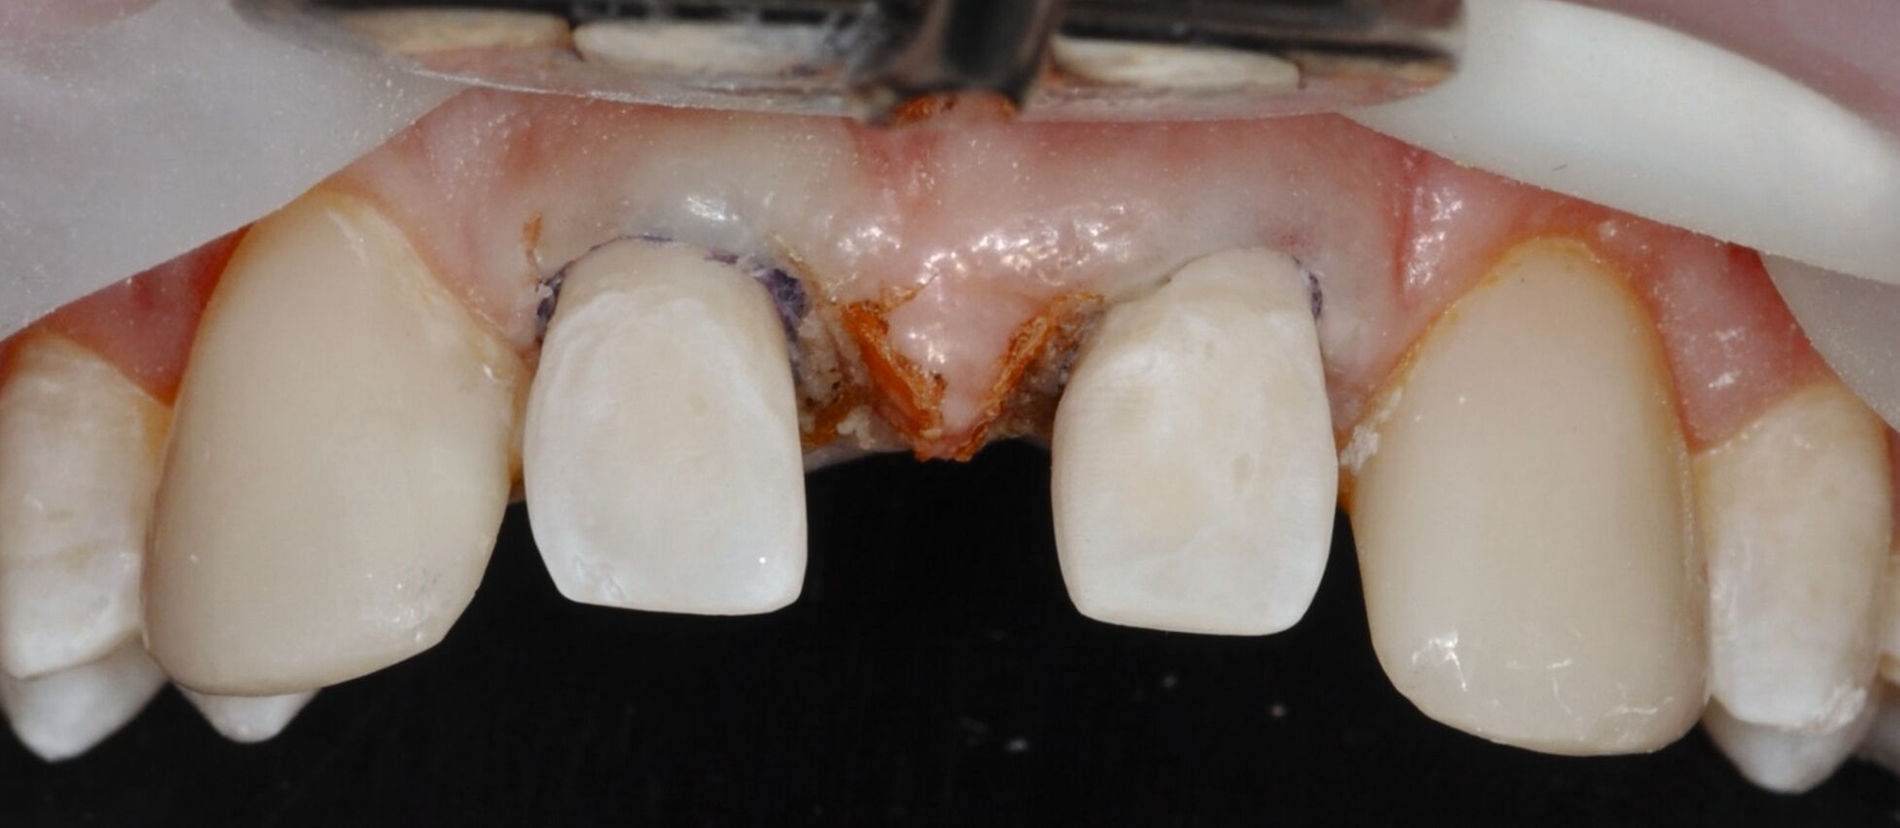

Anschließend werden laborgefertigte Non-prep-Kompositveneers aus dem gleichen Material für die Zähne 12 und 22 hergestellt. Diese werden in einer zweiten Sitzung nach dem Abstrahlen des Zahnschmelzes beziehungsweise der Restaurationsinnenflächen mit Al₂O₃-Pulver und dem Einbringen von Retraktionsfäden adhäsiv (IPS Empress Direct & Flow A2) eingesetzt. Zur Optimierung der Papillenästhetik wird der breite mediale Papillenbereich vor dem Einsetzen der Veneers durch eine externe Gingivektomie reduziert. Der marginale Gingivaverlauf der Zähne 12 und 22 wird unter Berücksichtigung der Lachlinie und in Absprache mit dem Patienten nicht nach apikal auf das Niveau der Eckzähne verlagert. Zusätzlich werden die Zähne 14 und 24 im Bereich der bukkalen Höckerspitzen direkt mit Komposit umgeformt und harmonisch an die neue Frontzahnsituation angepasst.

Die direkten und indirekten Kompositrestaurationen werden abschließend mit Skalpellen (Nr. 12), diamantierten Schallspitzen, rotierenden Instrumenten und Soflex-Scheiben ausgearbeitet, in statischer und dynamischer Okklusion kontrolliert, entsprechend eingeschliffen und auf Hochglanz poliert. Die Hygienefähigkeit der marginalen Bereiche wird sichergestellt und dem Patienten werden zur häuslichen Reinigung der Zahnzwischenräume passende Interdentalraumbürstchen angepasst (Abbildung 3).